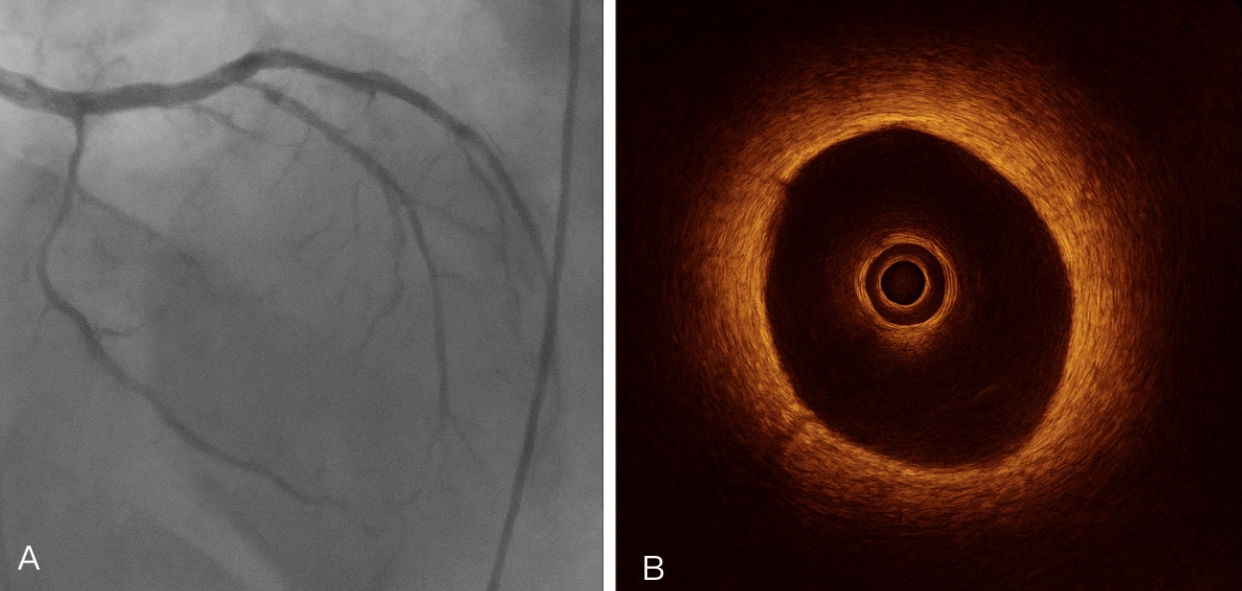

Spontaneous coronary artery dissection (SCAD) is a rare but important cause of acute myocardial infarction (AMI), particularly in young women without traditional cardiovascular risk factors. Early recognition and diagnosis using coronary angiography, supplemented by intravascular imaging such as intravascular ultrasound (IVUS) or optical coherence tomography (OCT), is essential for accurate diagnosis and management, which can range from conservative therapy to percutaneous or surgical intervention. We report the case of a 32-year-old woman who presented with acute chest pain and elevated cardiac biomarkers. Electrocardiography revealed ST-segment elevation in the anterior leads. Emergent coronary angiography demonstrated a mid-left anterior descending (LAD) artery dissection with preserved distal flow, which was confirmed by OCT. The patient was managed conservatively with dual antiplatelet therapy and beta-blockers. She remained stable, with resolution of symptoms and normalization of cardiac enzymes. Follow-up imaging at 3 and 12 months demonstrated complete healing of the dissected vessel. This case emphasizes the importance of considering SCAD in young women presenting with AMI, highlights the role of advanced coronary imaging in diagnosis and risk stratification, and supports individualized management strategies.